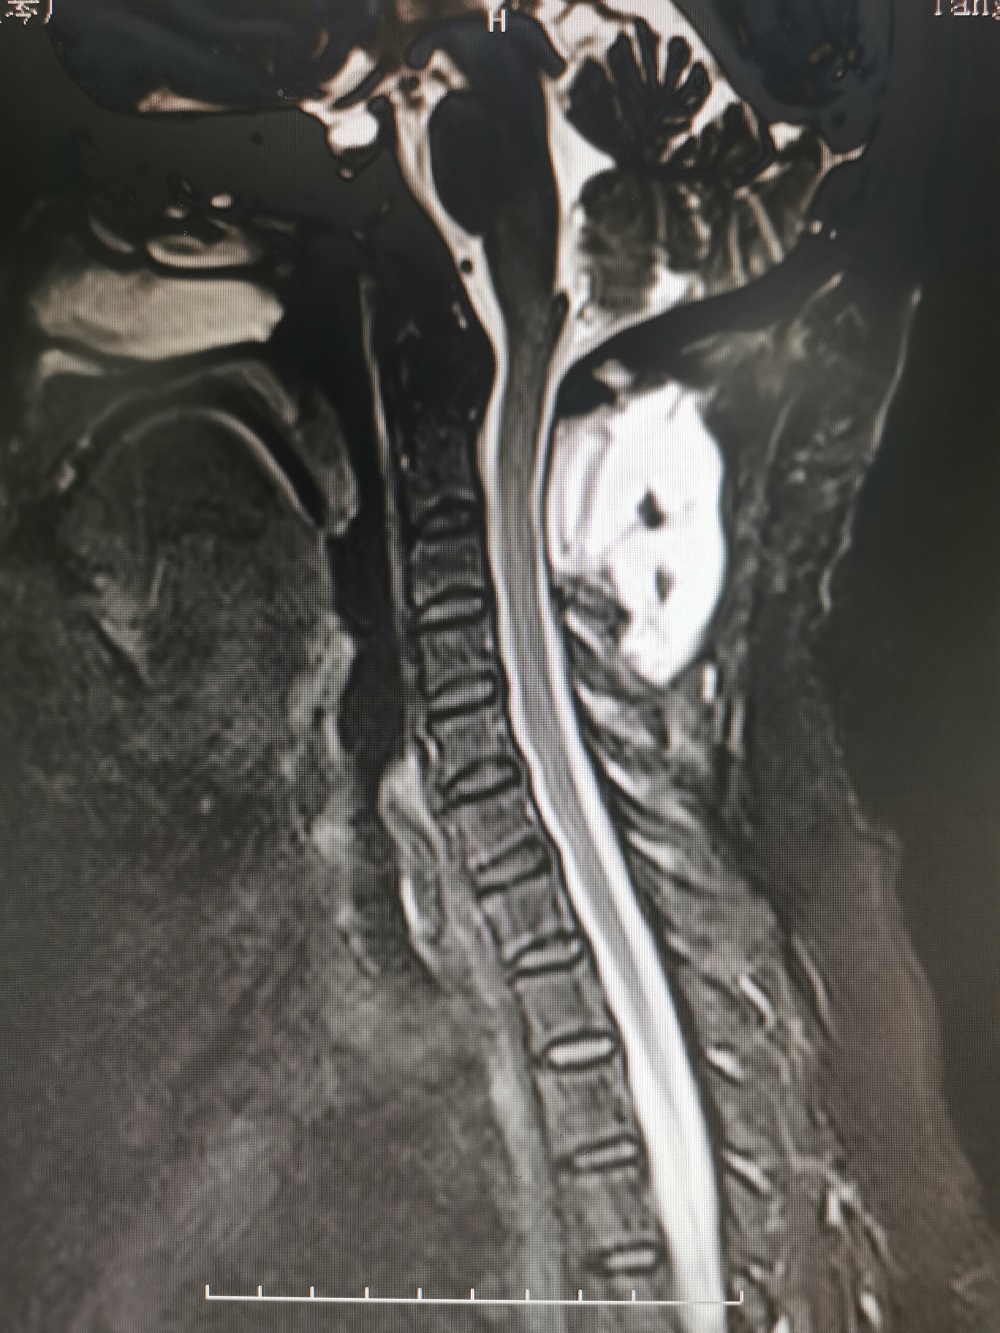

结果颈椎核磁共振检查发现,马女士颈2椎管内肿瘤(术后病理检查为脊膜瘤),颈5-6、6-7出现颈椎间盘突出,并且还有颈椎骨质增生。

术前影像学检查

鉴于目前马女士症状明显并且有加重迹象,从各项检查来看,椎管内肿瘤位于高颈段,脊髓受压严重,而且还伴有颈椎间盘突出和颈椎骨质增生,病情较为复杂,如果不积极治疗后果不堪设想。综合评定分析后,廖博主任建议马女士应该尽快手术治疗。